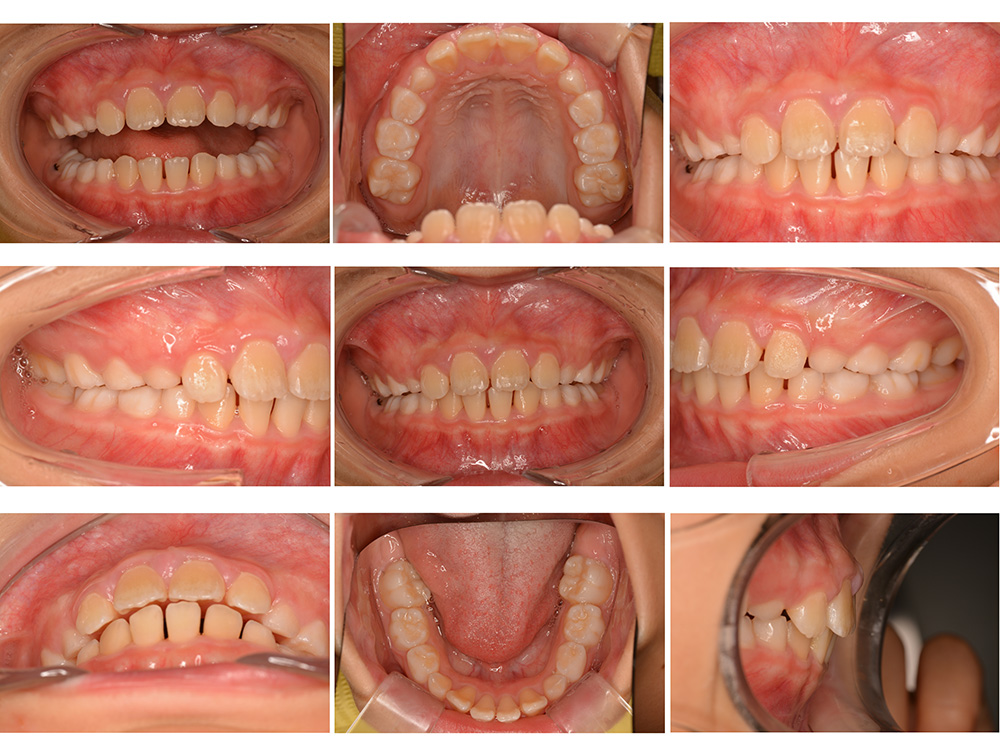

術前

術後

世代・性別

10歳女性

主訴

前歯が出ているのを治したい

治療内容

筋機能矯正治療(治療途中)

治療期間

4ヶ月

治療費

27万円(税別)

治療のリスク

歯の移動に伴う痛み